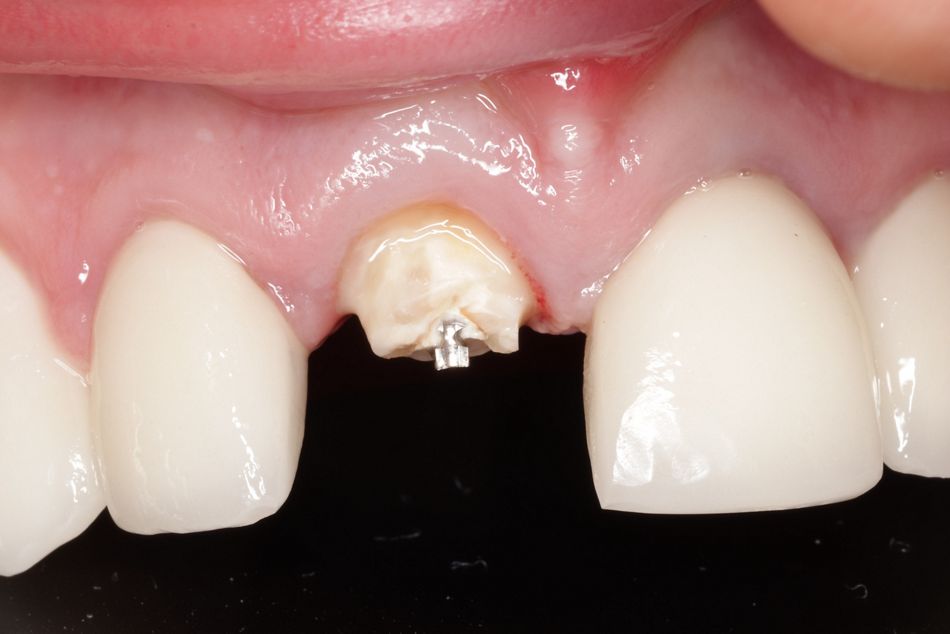

Der Patient konsultierte die Praxis mit einer frakturierten Keramikkrone an Zahn 21 (Abb. 1 und 2). Der junge Mann ist gesund, sportlich und legt hohen Wert auf eine ästhetische Verbesserung im Frontzahngebiet. Die Erstdiagnostik zeigte, dass die Zähne 12 bis 22 wurzelbehandelt und mit einem Kronenblock prothetisch versorgt waren. Die Restauration war zirka zehn Jahre alt.

Ein Jahr später erschien der Patient als Notfallpatient in der Praxis. Bei einem Unfall ist die Krone auf Zahn 11 frakturiert (Abb. 5). Grundsätzlich stellt sich in einem solchen Fall die Frage nach dem Versuch eines Zahnerhalts oder der Zahnextraktion. In diesem Fall musste die Vorhersagbarkeit eines Zahnerhalt-Versuchs als gering beurteilt werden. Daher fiel die Entscheidung für die Extraktion mit anschließender Sofortimplantation. Durch die Sofortimplantation sollte einer umfangreichen Knochenresorption und einem starken Rückgang des Weichgewebes vorgebeugt werden. Wesentliches Argument für diesen Therapieweg war zudem die kürzere Behandlungsdauer und das minimalinvasive Vorgehen. Klinisch sprach nichts gegen eine Sofortimplantation (entzündungsfreie Alveole, unversehrte labiale Knochenlamelle). Der Patient willigte dem Vorgehen ein.